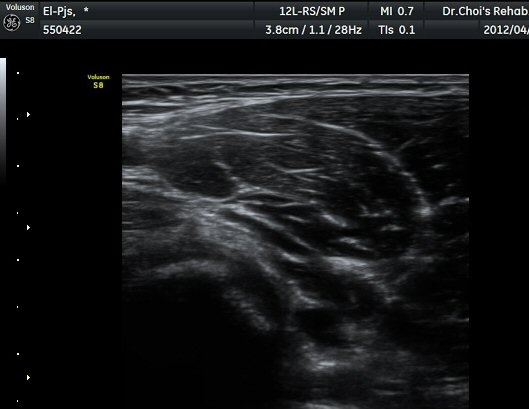

ŽÃËÀÚ¸¦ ÆÈ²ÞÄ¡ ¸»´ÜÀ¸·Î À̵¿ÇÏ´Ï À̵ιڱ٠ÈûÁÙÀÇ ºñÈÄ¿Í ÈûÁÙ ÁÖÀ§¿¡ Àú¿¡ÄÚ ¼ö¾×Àú·ù°¡ ]

°üÂûµÈ´Ù(±×¸² 2, 3, 4, 5). ŽÃËÀÚ¸¦ ¸»´ÜÀ¸·Î À̵¿ÇÒ ¶§ ŽÃËÀÚ¸¦ ¸Ó¸®ÂÊÀ¸·Î °æ»ç(tilting)½ÃÄѾß

À̵ιڱ٠ÈûÁÙ¿¡ Á÷°¢ ÀÇ ÃÊÀ½ÆÄ Á¶»ç°¡ °¡´ÉÇÏ¿© À̵ιڱ٠ÈûÁÙÀÌ °í¿¡ÄÚ·Î °üÂûµÈ´Ù.